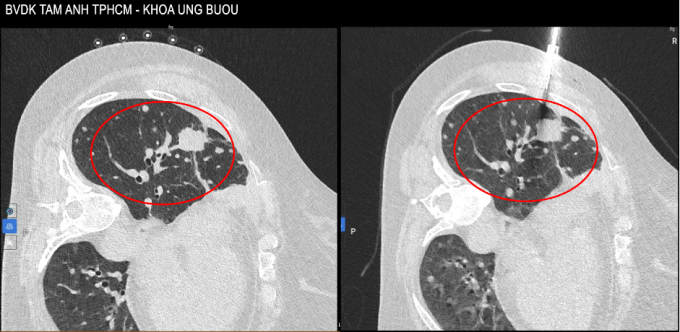

Hình ảnh CT vào tháng 10/2025 cho thấy u tăng kích thước lên 4 cm và các tổn thương rải rác xung quanh. Ảnh: Bệnh viện Đa khoa Tâm Anh

Bà bị đau ngực nhiều hơn, tháng 10 năm nay chụp CT phát hiện tổn thương tăng kích thước lên 4 cm. Bác sĩ chỉ định sinh thiết u phổi để tìm đột biến gene kháng thuốc. Kết quả giải phẫu bệnh và nhuộm hóa mô miễn dịch sau hai lần sinh thiết cho thấy có đột biến T790M trên gene EGFR và một số đột biến khác trên gene mTOR, TP53, làm tăng độ phức tạp của tình trạng bệnh.